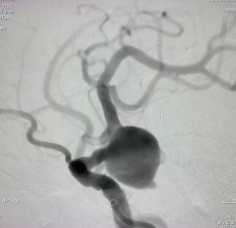

生死时速!造影剂过敏险丧命,市一专家“脱敏”手术破解颅内“不定时炸弹”